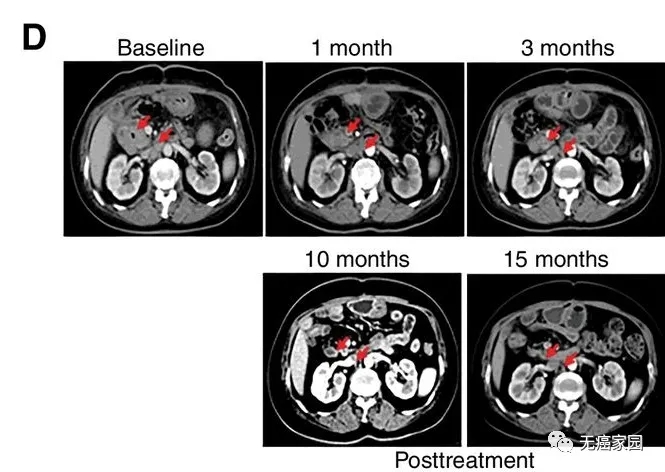

在2018年3月,解放军总医院韩卫东教授的团队公布了利用EGFR CAR-T技术治疗胆道系统肿瘤的初步结果。

此次纳入的患者均为EGFR强阳性(>50%的癌细胞表达EGFR)的不可切除的胆道系统恶性肿瘤患者,共纳入19例患者,包括胆管癌14例,胆囊癌5例。

研究结果显示,17例患者可评估,其中1例胆管癌患者的肿瘤完全消失,截止到目前疗效已经保持了22个月,尚未发现疾病复发。10例患者疾病稳定,疗效保持2.5~15.5个月,中位无进展生存期为4个月。

CART-RGFR细胞治疗之前和1、3、10和15个月患者1的CT扫描图像。

红色箭头表示原发肿瘤和腹膜后淋巴结转移。